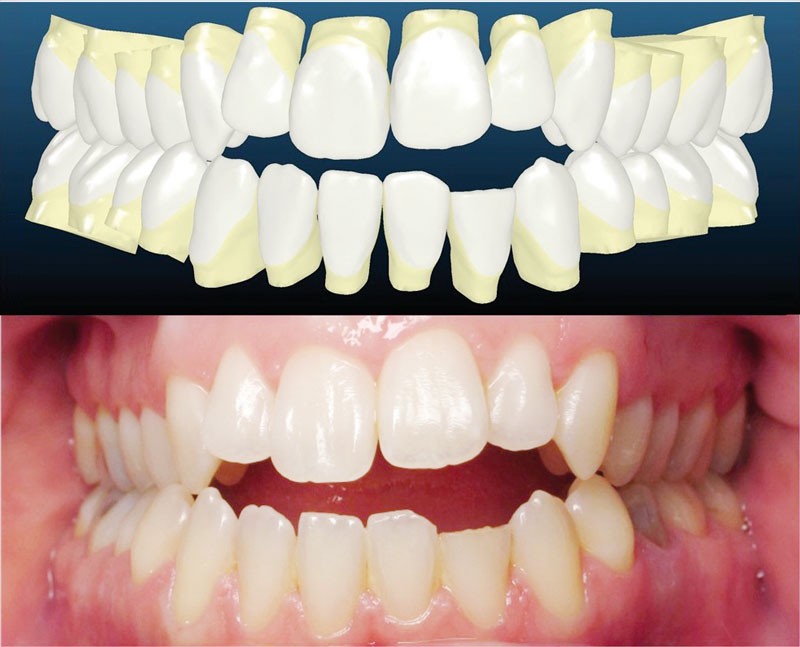

Le set up Insignia

Les empreintes ont été réalisées en sillcone wash technique et adressées au laboratoire Insignia. Actuellement, nous réalisons ces empreintes à l’aide de la caméra intra-orale Lythos et la fiche patient est initialement créée sur la caméra. Le transfert des empreintes au laboratoire est immédiat et le risque d’erreurs considérablement réduit (fig. 4 à 6).

L’esthétique faciale de la patiente s’est nettement améliorée (fig. 7, 8, 9 et 10). On remarquera la réduction du sourire gingival…